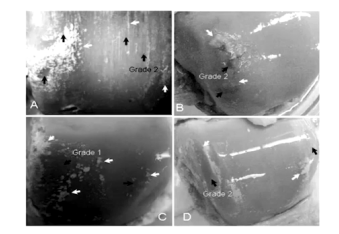

2)超声:肾脏超声提示左肾囊肿,前列腺增生。关节超声显示,右足第一跖趾关节腔滑膜增厚,有少量积液;左足第一跖趾关节腔有少量积液,第一趾骨远端表面可见双轨征;双侧踝关节未见明显异常;左、右膝关节提示劳损性改变;左右腕关节背侧滑膜增厚。

(2)常规超声检查可显示痛风性关节炎的特异性图象表现,有临床应用价值,必要时可行介入穿刺及病理明确诊断。